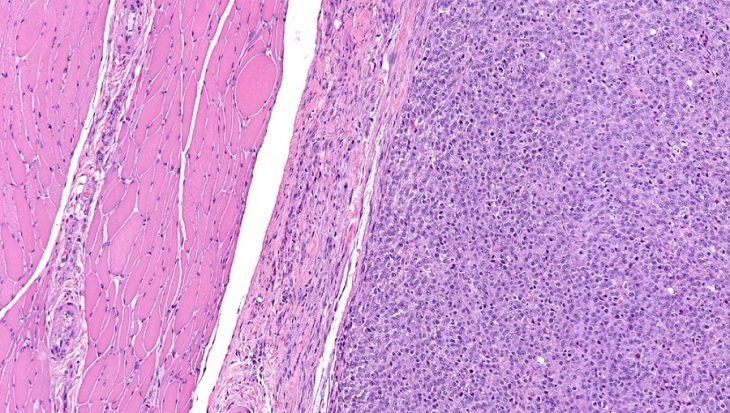

В основе возникновения опухоли лежит бесконтрольное деление клеток поперечно-полосатой мышечной ткани, которые имеют аномальное строение, отличающееся от структуры нормальных мышечных клеток (миоцитов). При их рассмотрении под микроскопом отмечается их схожесть с клетками 7-10-недельного эмбриона – рабдомиобластами.

Эмбриональная рабдомиосаркома представляет собой четко ограниченный узел с мясистой (иногда более мягкой) консистенцией, в котором присутствуют очаги кровоизлияний и омертвения тканей. Диаметр такого новообразования может составлять от 1 до 32 см.

Специалисты выделяют четыре морфологических типа такой злокачественной опухоли:

- Веретеноклеточный. Название такого типа опухоли указывает на форму атипичных клеток. Чаще появляется у мальчиков и обычно локализуется на голове, шее, тканях яичек или в других местах.

- Ботриоидный. Опухоль представляет собой дольчатый или полипообразный узел со слизистой оболочкой, под которой находится гиперцеллюлярная зона с более разреженным расположением клеток. Обычно выявляется в мочеполовых органах (иногда в других местах). Составляет около 10 % от всех эмбриональных рабдомиосарком.

- Анапластический. Новообразование состоит из клеток причудливой формы (иногда в виде гигантских многоядерных элементов). Чаще выявляется в мягких тканях ног, но может образовываться в яичках или других местах. Обнаруживается крайне редко.

- Альвеолярный. Опухоль представляет собой мягкий узел бело-желтого цвета с диаметром от 2 до 8 см, состоящий из клеток разного размера (мелких, крупных, гигантских), собирающихся в гнезда или скопления и разделяющихся фиброзными прослойками. В тканях новообразования могут выявляться зоны некроза. Обычно располагаются на шее, голове, туловище, в тазовой области или в других местах. Чаще появляются у детей до 10 лет, но могут возникать и у лиц молодого возраста.